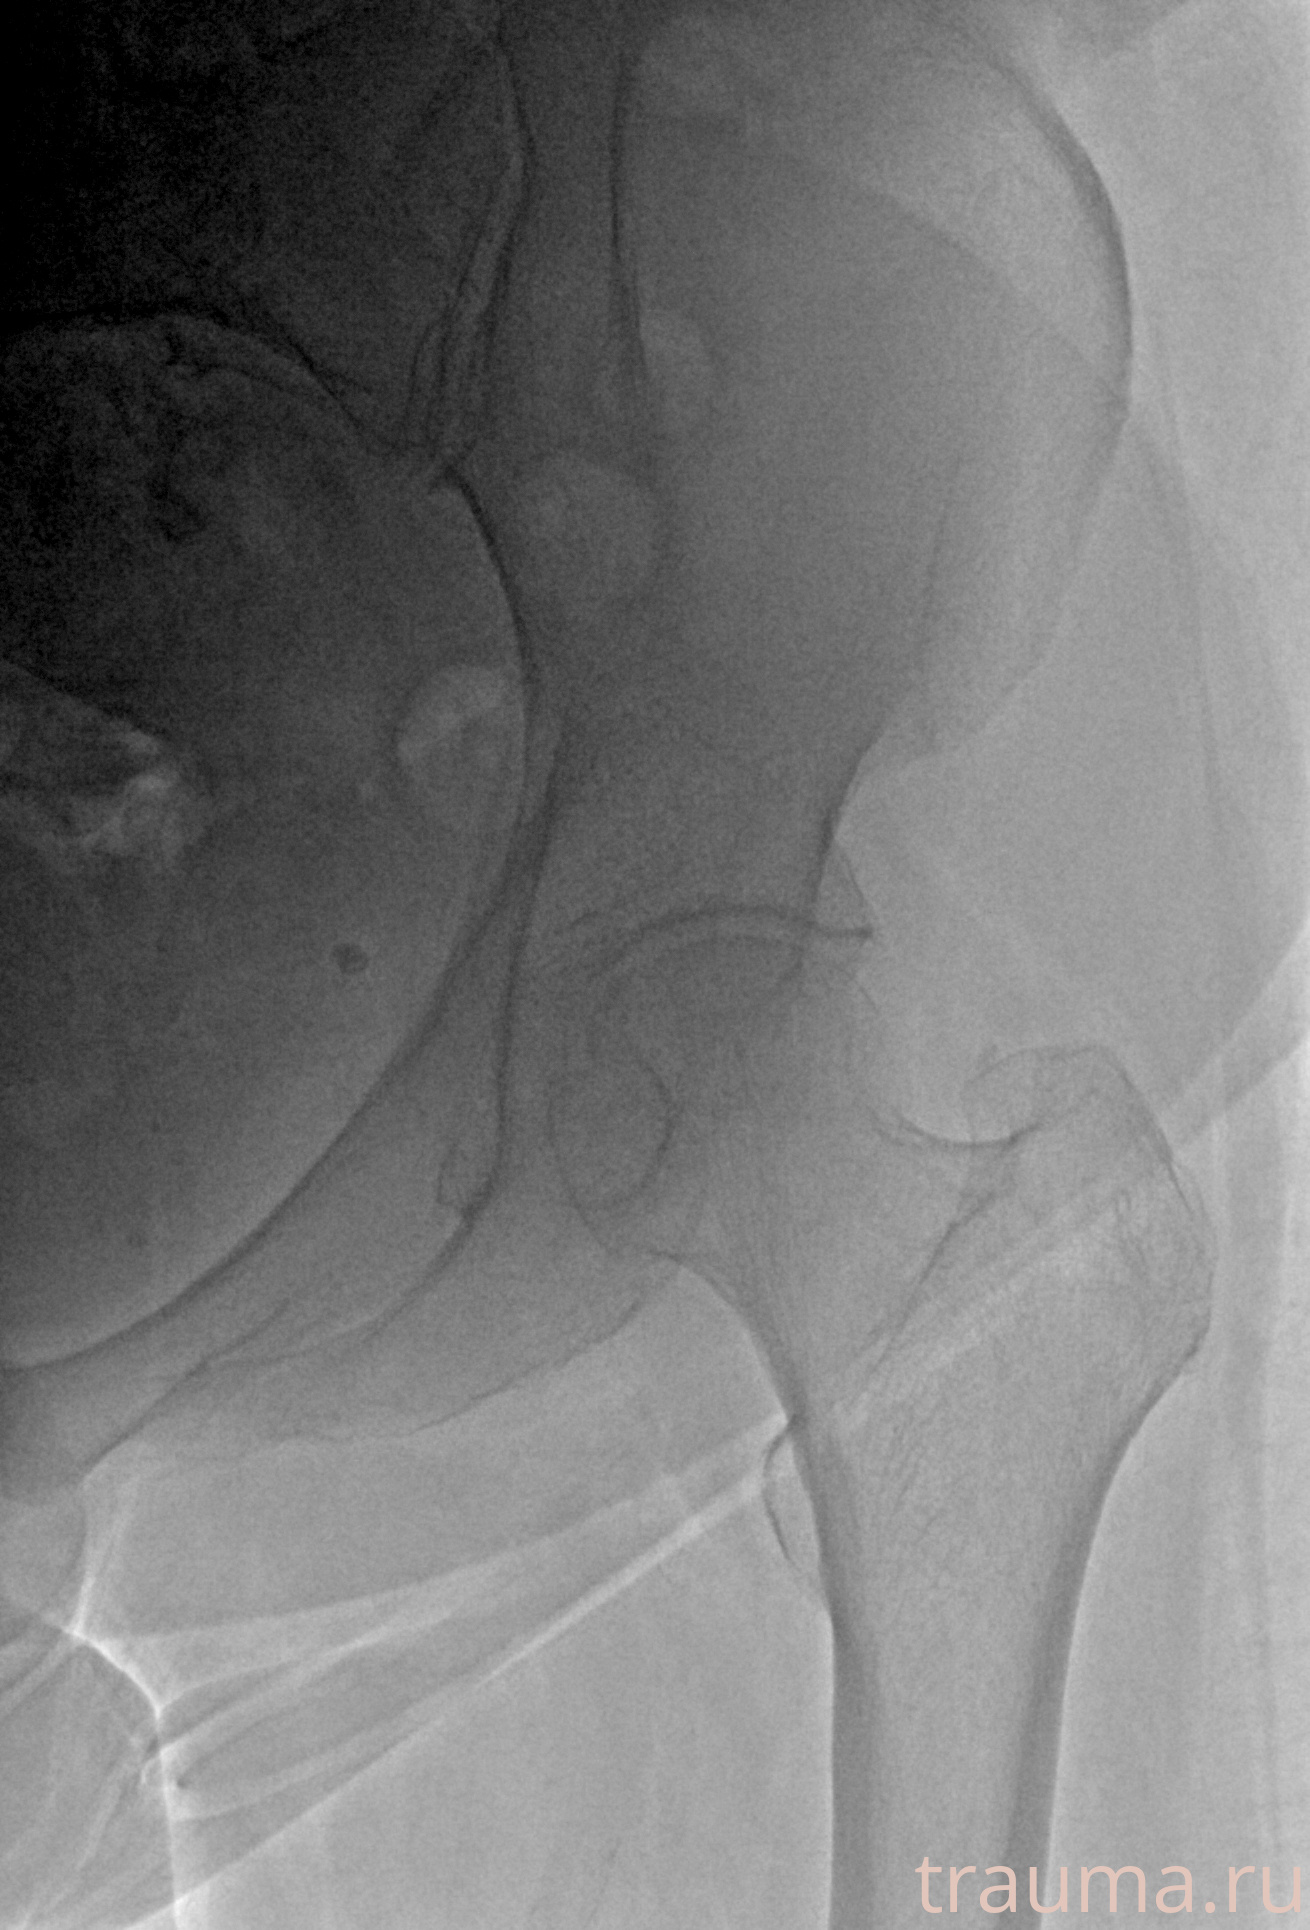

Рентгенограммы

Рентген на дому: по вашему адресу приезжает врач-рентгенолог, травматолог-ортопед с мобильным рентгеновским аппаратом, проводит диагностику травмы или заболевания, делает необходимые рентгенограммы, дает рекомендации по дальнейшему лечению. Получить качественные снимки в домашних условиях возможно благодаря уникальной методике, разработанной МосРентген Центром для института  Склифосовского